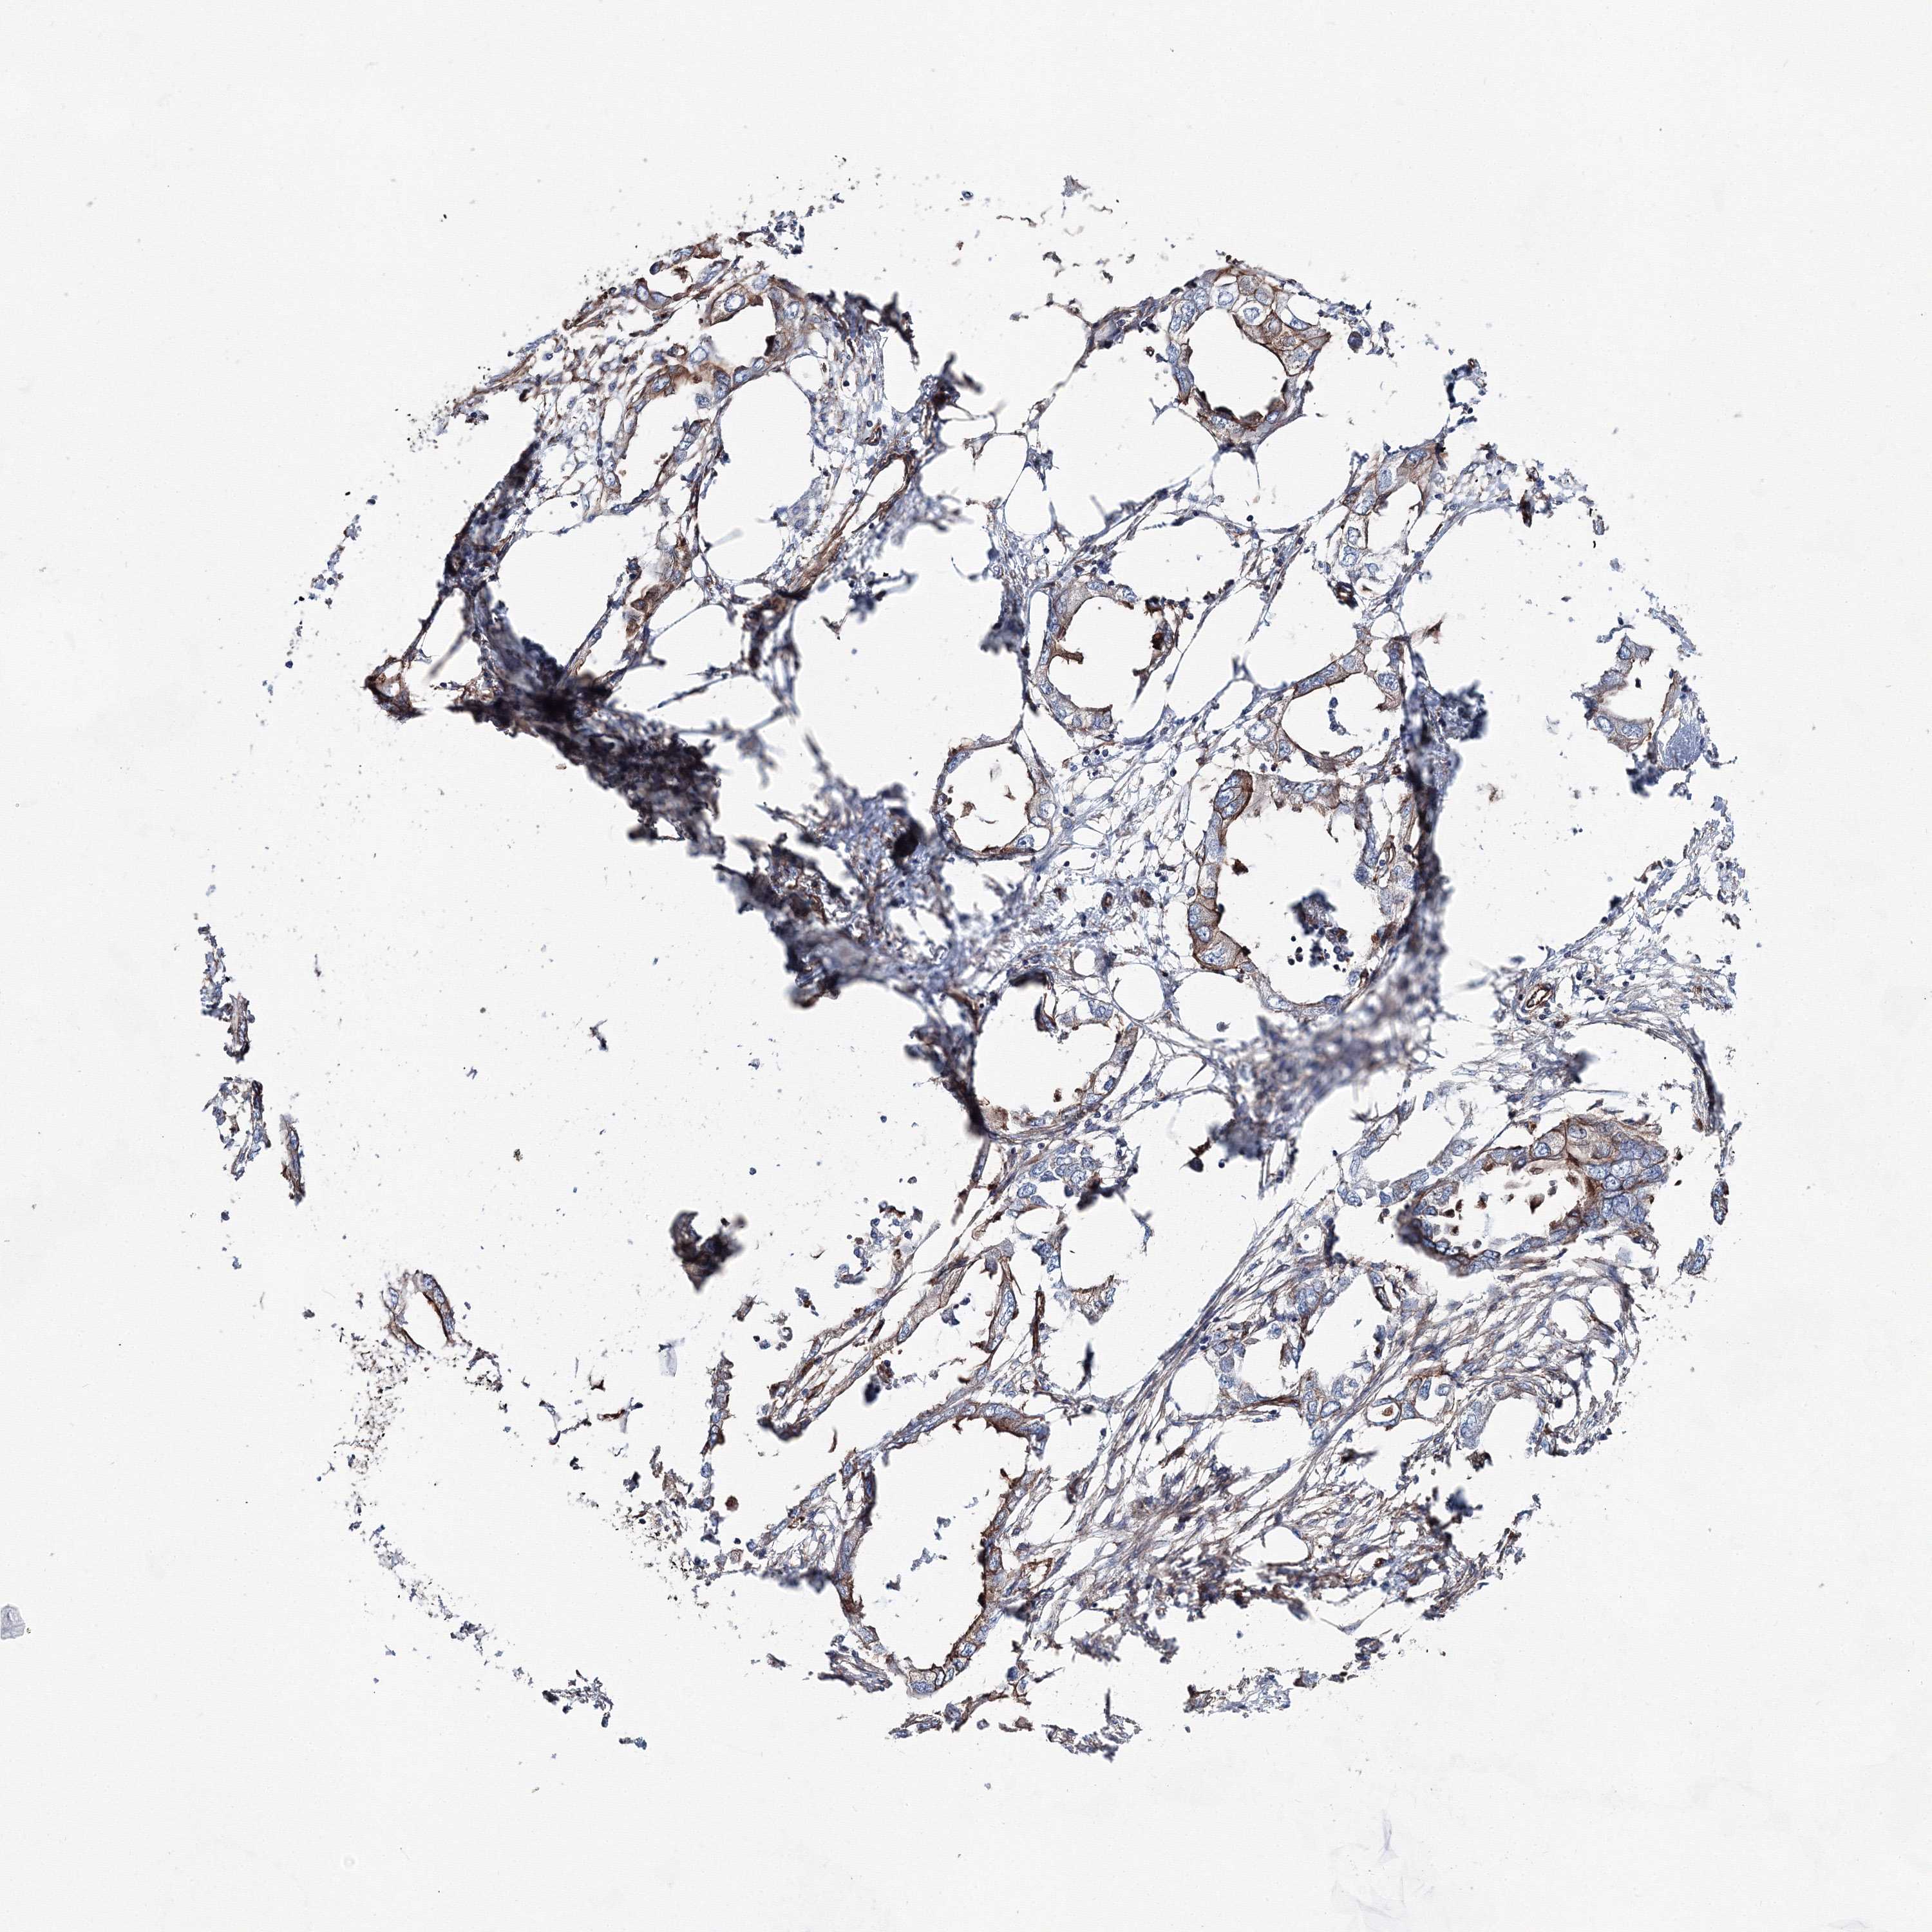

ENDOMETRIAL CANCER - Protein expressioni

A mouse-over function shows sample information and annotation data. Click on an image to view it in a full screen mode. Samples can be filtered based on level of antibody staining by selecting one or several of the following categories: high, medium, low and not detected. The assay and annotation is described here.

Note that samples used for immunohistochemistry by the Human Protein Atlas do not correspond to samples in the TCGA dataset.

Antibody stainingi

Antibody staining in the annotated cell types in the current human tissue is reported as not detected, low, medium, or high, based on conventional immunohistochemistry profiling in selected tissues. This score is based on the combination of the staining intensity and fraction of stained cells.

Each image is clickable and will lead to virtual microscopy that enables deeper exploration of all samples and also displays staining intensity scores, fraction scores and subcellular localization as well as patient and tissue information for each sample.

Antibody HPA036626

Antibody HPA058127

Staining

High

Medium

Low

Not detected

Intensity

Strong

Moderate

Weak

Negative

Quantity

>75%

75%-25%

<25%

None

Location

Nuclear

Cytoplasmic/membranous

Cytoplasmic/membranous,nuclear

Adenocarcinoma, NOS

Adenocarcinoma, metastatic, NOS